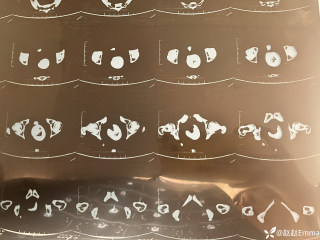

昨天值班遇到的一例晕厥病例,差点漏诊,而最终的解法,始于最简单而质朴的查体。国庆中秋双节的最后一天,8号的早上8点,抢救室床旁晨交班,病人依旧是多而重,交到6床,一个刚入室不久的病人,准备去做CT,夜班医师汇报病史:69岁男性,本次因“头晕伴一过性晕厥1小时”为主诉入抢,1小时前于高铁站因即将赶不上高铁走路快时突发头晕,伴一过性晕厥,约3-4分钟后清醒,清醒后诉今晨未吃早餐,已服用降压药物,仍有头晕头痛、四肢乏力等不适,无胸闷胸痛,无畏寒发热,无咳嗽咳痰,无恶心呕吐,无肢体麻木,无视物模糊等不适,路人拨打120送至我院急诊就诊。既往高血压,长期服用氨氯地平+福辛普利,血压控制一般;糖尿病,长期